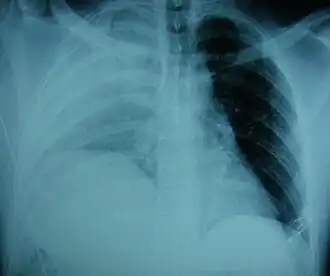

Los exámenes físicos no son precisos, ya que no suele haber ningún signo físico específico que pueda usarse para diagnosticar esta afección.[3] Los métodos toracoscópicos y laparoscópicos pueden ser precisos.[12] Se sabe que la radiografía de tórax no es fiable para diagnosticar la rotura diafragmática;[4] tiene baja sensibilidad y especificidad para la lesión.[5] A menudo, otra lesión, como una contusión pulmonar, enmascara la lesión en la placa de rayos X.[6] La mitad de las veces, las radiografías iniciales son normales; en la mayoría de las que no lo son, hay hemotórax o neumotórax.[4] En la placa puede aparecer una sonda nasogástrica procedente del estómago en la cavidad torácica; este signo es patognomónico de rotura diafragmática, pero es poco frecuente.[4] La radiografía es más capaz de detectar la lesión cuando se toma de espaldas con la persona erguida, pero esto no suele ser posible porque la persona no suele estar lo suficientemente estable; por lo tanto, suele tomarse de frente con la persona tumbada en decúbito supino.[5] La ventilación con presión positiva ayuda a evitar que los órganos abdominales se hernien en la cavidad torácica, pero esto también puede impedir que se descubra la lesión en una radiografía.[4]